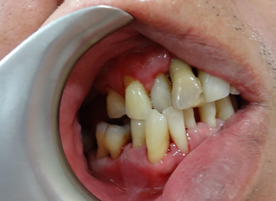

This is how his dentition and gum condition when he first saw me. Scaling was done prior to photo taking. His oral hygiene was compromised, and one of the upper front incisor is wobbly, with gum boil. Thorough examination for his teeth and gum was done. He wanted gum therapy and hope to save his other teeth, if possible. He also understood that gum therapy is a tedious procedure and needs his co-operation in term of good ora hygiene home care routine.

It is a always a standard procedure to take X-ray and periodontal charting (to measure the ‘cuff’ of gum around each tooth to see if there is any sign that periodontal disease has started and the severity) as a baseline record. X-ray is needed to see the amount of bone that has been lost. We did the same thing for this gentleman, severe bone loss was noticed at the lower front teeth region but he refused to extract them. The lower front teeth are loose but did not disturb his chewing, and most importantly, there was no active infection. After discussion, we decided to keep them and will only remove them in future if worsening. Those were considered hopeless teeth.